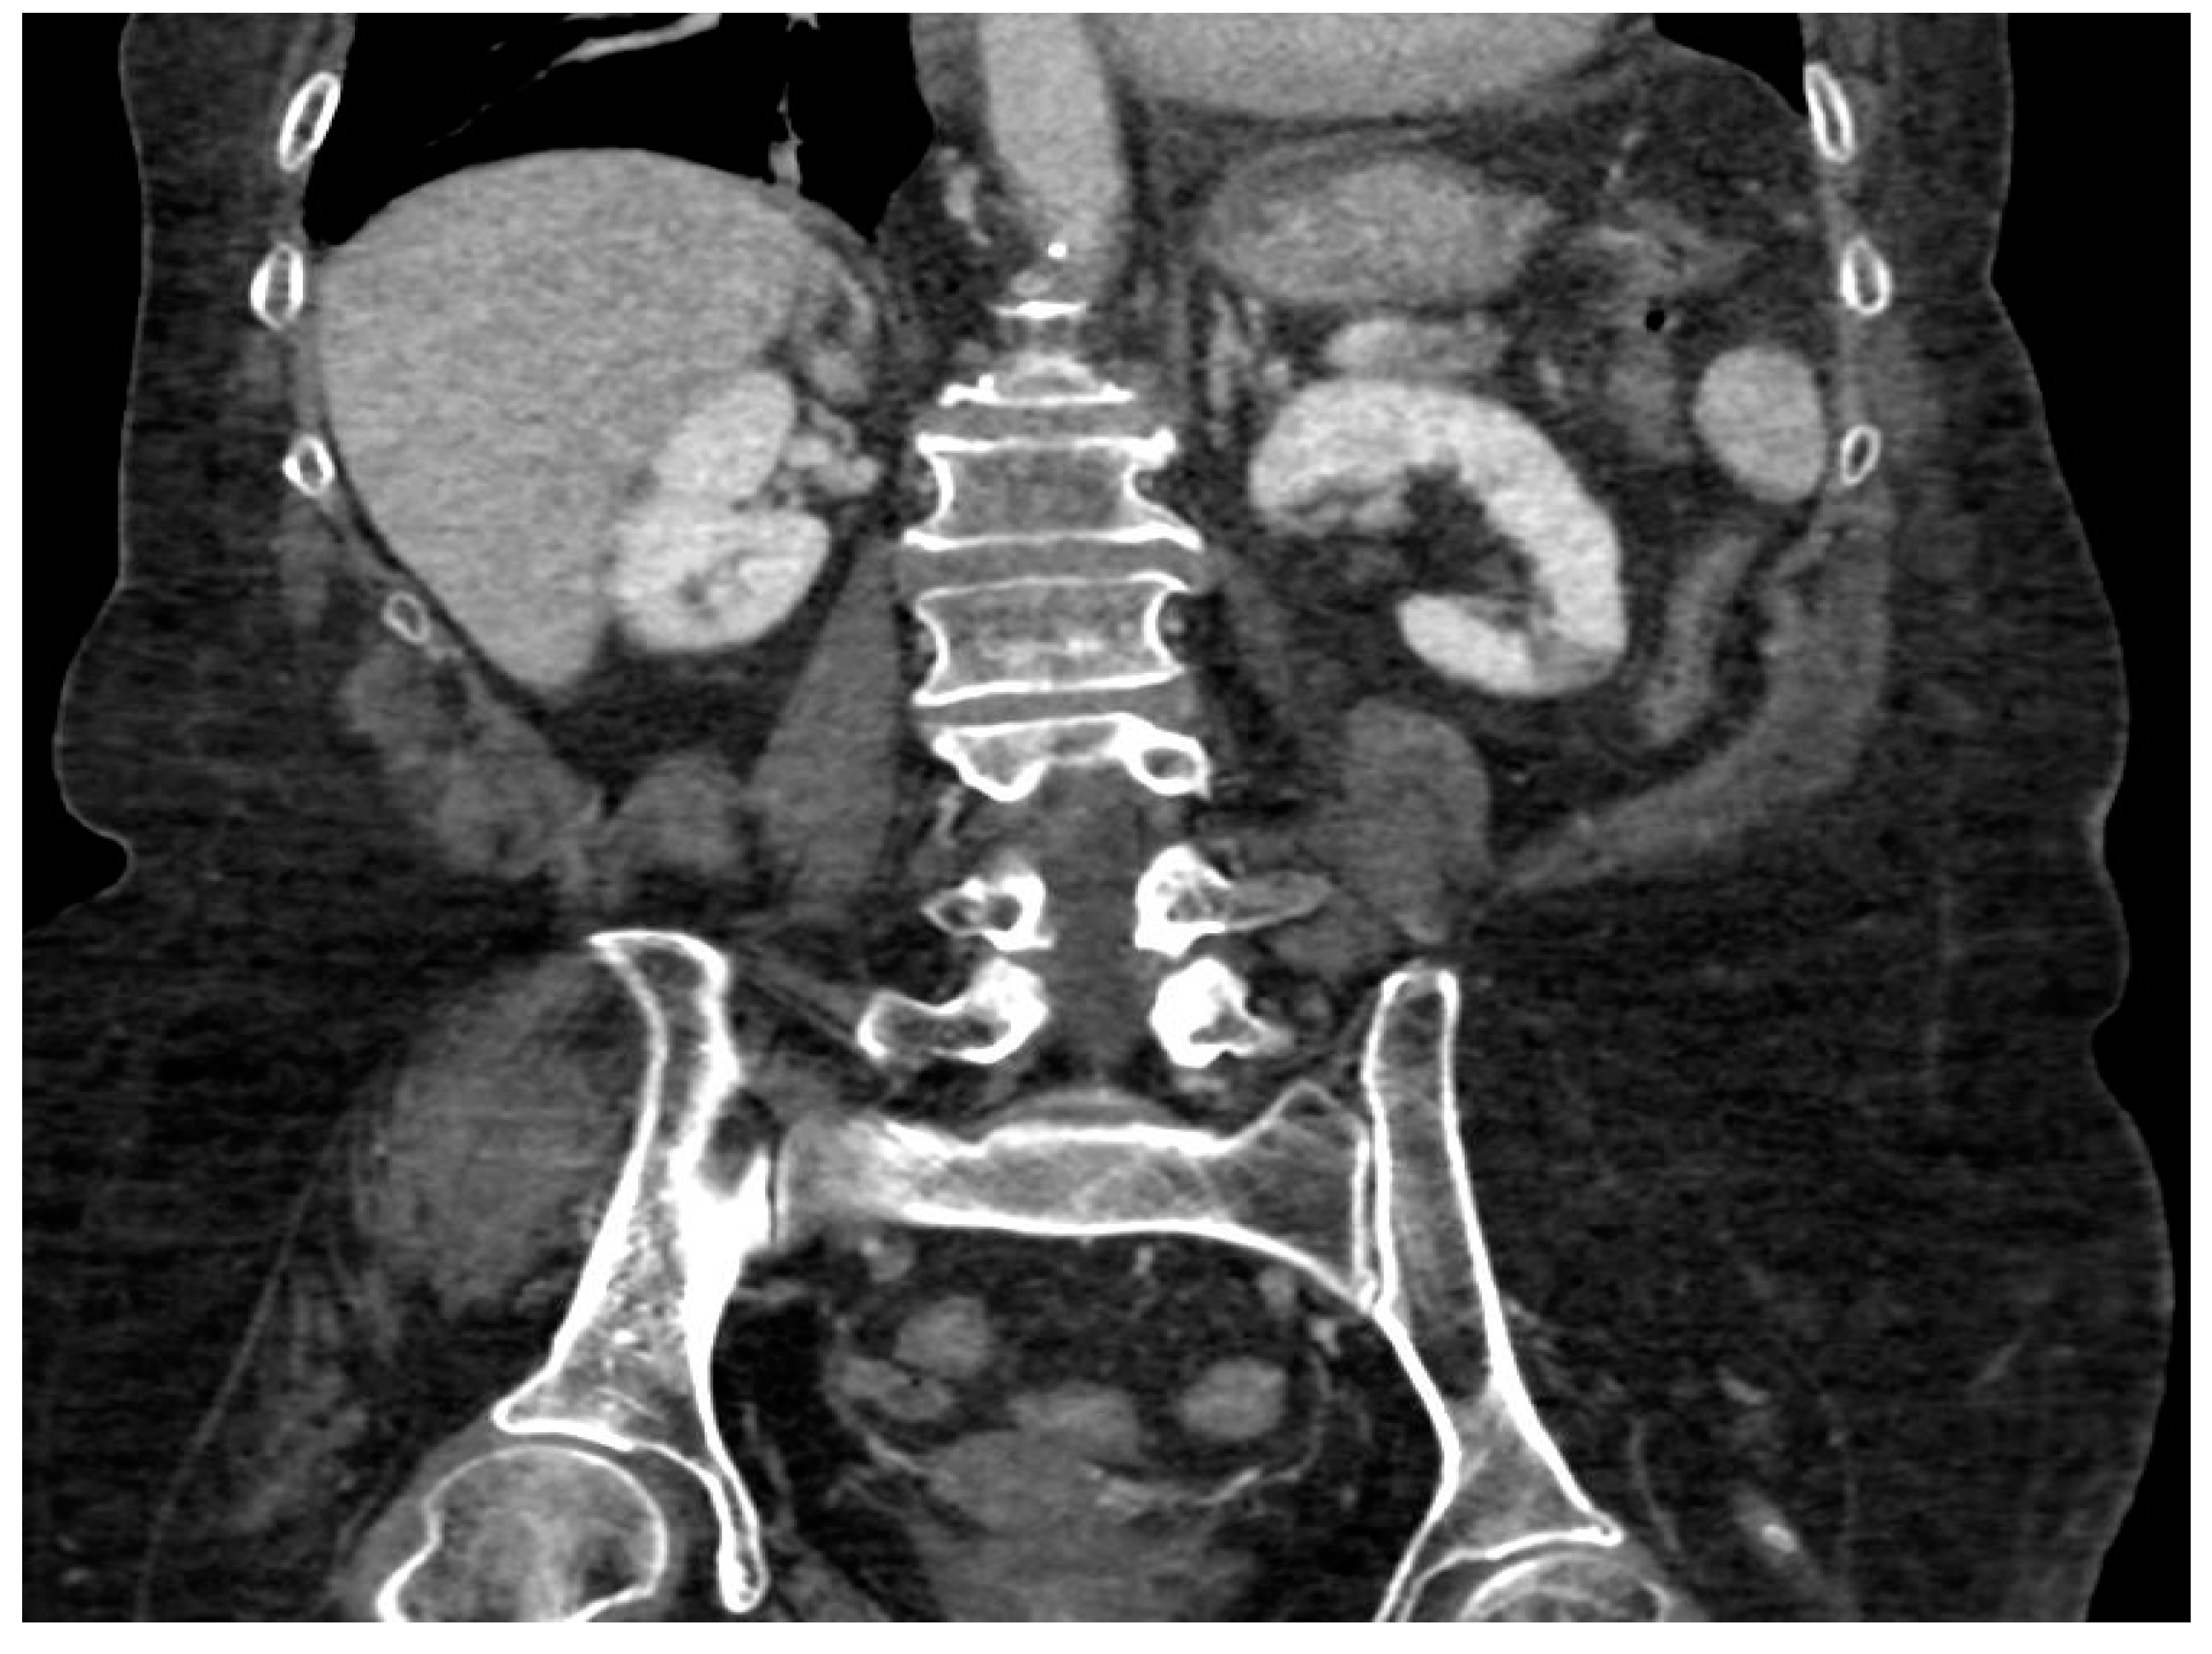

- Focal ischemia of the left renal parenchyma in four patients (36.4%) (Figure 3);

| 9/11 | Subrenal aorta to common iliac arteries bilaterally | 81.8% |

| 2/11 | Infrarenal aorta to common iliac arteries bilaterally | 18.2% |